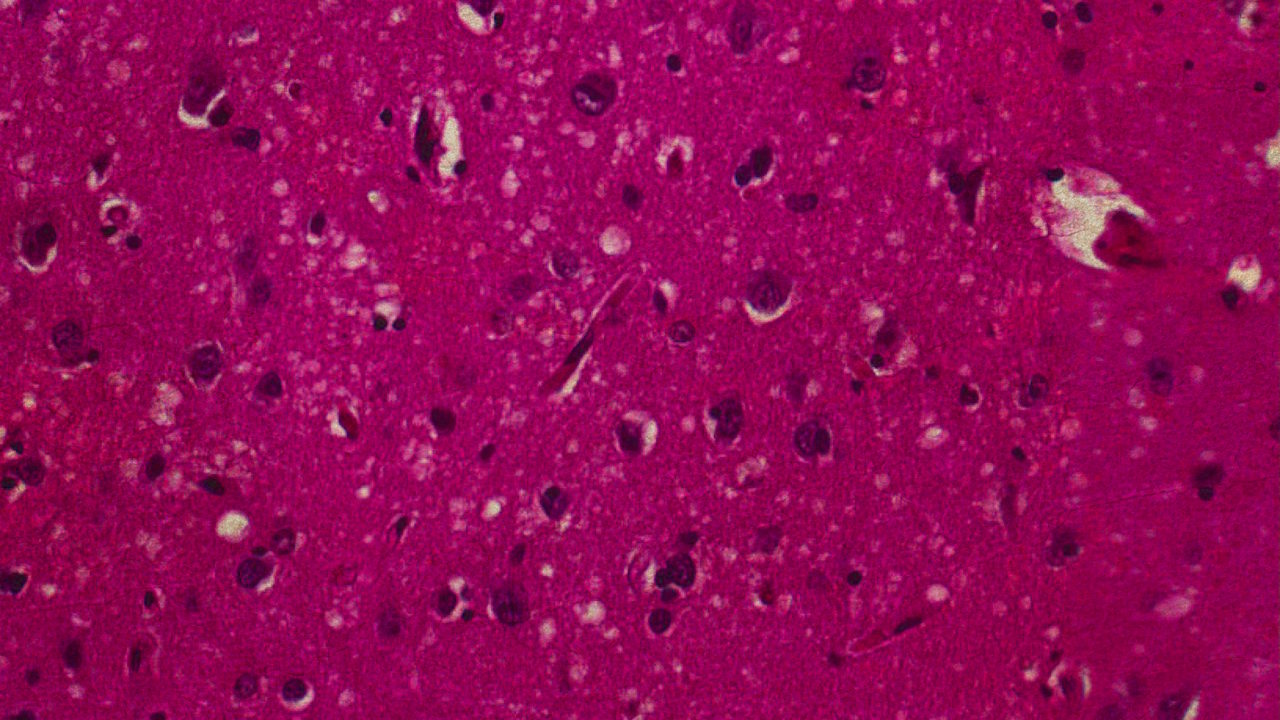

Іноді ці білки спонтанно втрачають нормальну форму і натомість набувають аномальної, шкідливої структури. Ба більше, такі неправильні пріони здатні перетворювати здорові білки на подібні до себе, таким чином їхня кількість неконтрольовано збільшується. Пріони утворюють міцні скупчення, які перешкоджають життєдіяльності клітин, тож ті гинуть, а мозкова тканина стає пористою, наче губка. Організм не сприймає пріони як загрозу і не вмикає імунну відповідь, адже зчитує їх як природну частину себе. Ферменти, які вміють розщеплювати білки, у цьому випадку безсилі: структура пріонових скупчень настільки стабільна й захищена, що вони просто не можуть подіяти.